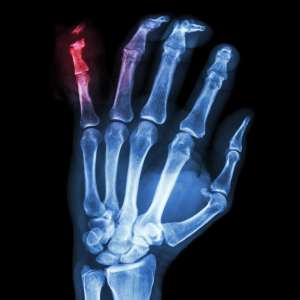

What is a Fracture?

- Fractures are the same as a “broken bones” and often occur due to a high energy injuries or fall, however sometimes they can occur through minor incidents if the bone has been weakened for some reason such as osteoporosis or stress fractures can occur from repetitive trauma.

- Bones often can heal without surgical fixation with the use of braces or casts.

- Sometimes to ensure the fracture can heal in an optimal position or allow early mobilisation surgical fixation is required.